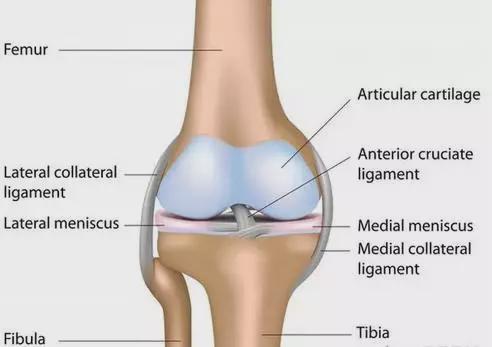

1、膝关节前麻痹或肌力低下型(因股四头肌麻痹或肌力低下开yun体育官网入口登录app,导致腘绳肌力量减弱开yun体育官网入口登录app,膝关节在伸展位时无法稳定,膝关节被迫在伸展位行走承受重量时)

2.膝后侧麻痹或肌力低下型(腘绳肌和小腿三头肌均麻痹或肌力低下,膝后侧包括关节囊、韧带等松弛,可引起膝关节过伸)

3、膝关节本身骨骼发生变化,导致膝关节位置异常。

二、膝关节角弓反张的原因分析

1、小腿三头肌张力过高,导致踝关节背屈受限

5、伸肌力与屈肌力严重不平衡,即屈肌力过小。